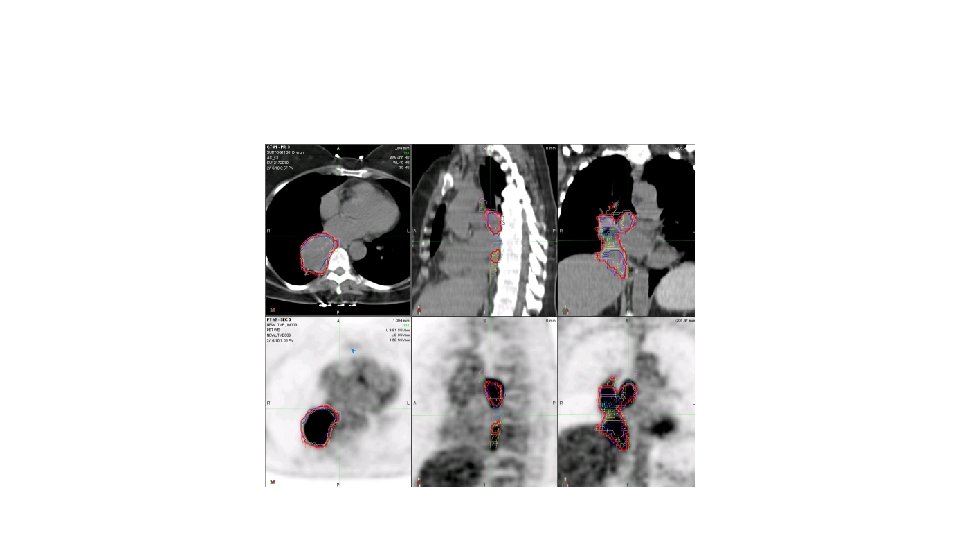

Radyoterapi • Günümüzde minimum 3 -B konformal RT standarttır. • Hedef Hacimler • GTV= Tm (Kontrastlı BT & 18 -FDG-PET-BT ) • CTV= GTV+ 6 mm (SCC)/ GTV+8 mm (Adenoca) • PTV= CTV+10 -30 mm (Solunum takibi yapılamıyorsa)

Atlases for CT Gross Tumor Volume (CTGTV) and PET Metabolic Tumor Volume (PETMTV) for RTOG 1106 Feng-Ming (Spring) Kong MD Ph. D, Ying Xiao Ph. D, James Galvin D. Sc, Randall Ten Haken Ph. D, Mitchell Machtay MD Jeffrey Bradley MD